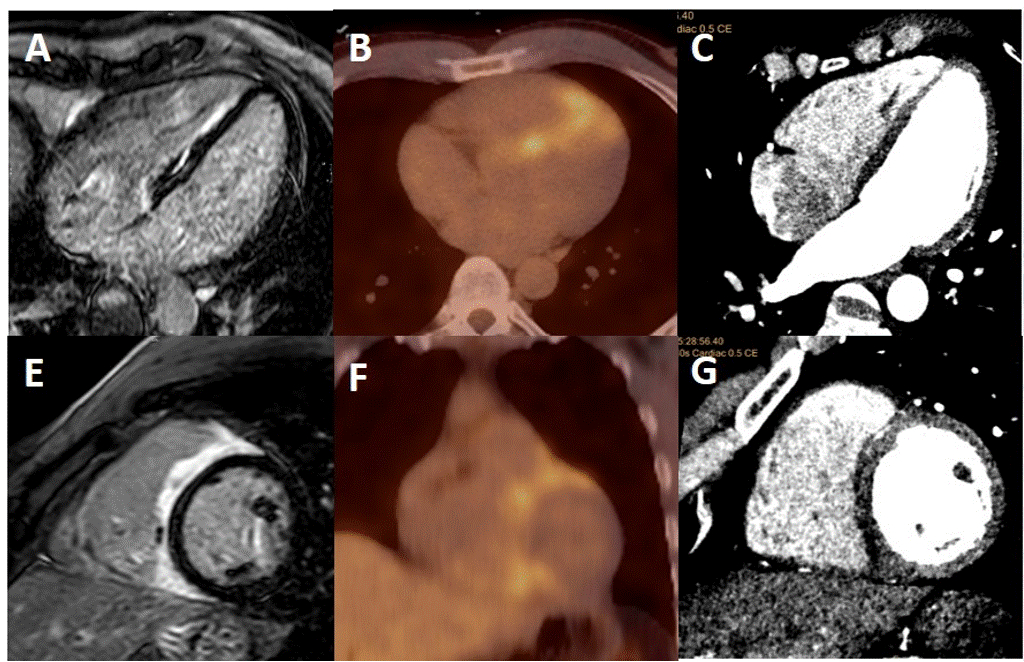

Cardiac MRI (cMRI) demonstrated late gadolinium enhancement (LGE) in the right ventricular aspect of the interventricular septum on T1 sequences not confined to a typical coronary territory. Positron emission tomography (PET) with fludeoxyglucose (18F-FDG) showed increased avidity in the same region without extracardiac uptake. A coronary computed tomography (CT) angiogram also showed decreased attenuation of the same region without CAD or coronary anomalies. Pathology from an endomyocardial biopsy showed dense lymphocytic and eosinophilic infiltrate with multinucleated giant cells without granulomas, consistent with GCM.

Three months later, the patient was appropriately shocked for sustained VT. Repeat PET had unchanged FDG-avidity, for which mycophenolate was added. Six-month follow-up was negative for ventricular arrhythmias. Repeat PET demonstrated complete resolution of FDG-avidity.

GCM requires prompt diagnosis and treatment to prevent mortality and morbidity. While endomyocardial biopsy remains the gold standard for diagnosis, non-invasive imaging allows for earlier diagnosis and assessment of response.